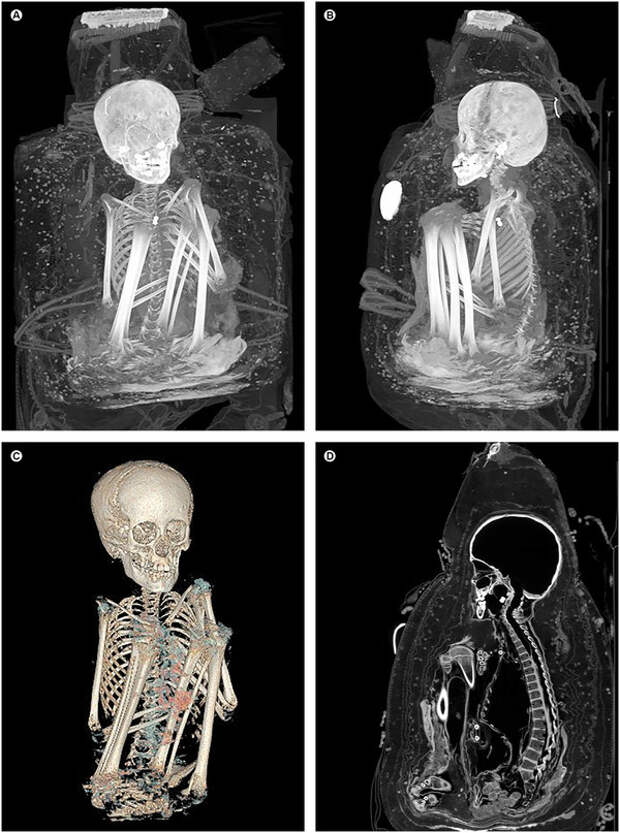

Недавно, с разрешения музея, экспонат с инвентарным номером IVc 2813 был изучен методом компьютерной томографии, который сейчас широко применяется для неинвазивного исследования археологических объектов. Оказалось, что внутри свертка находится тело мальчика 7–9 лет (возраст определили по зубам и костям). Оно закреплено в сидячем положении, с подогнутыми к груди ногами, при помощи плотной подстилки и веревок и тщательно обернуто тканью.

Тело не было специально мумифицировано: внутренние органы оставлены на месте, нет следов обработки бальзамическим составом. Вероятно, мумификация произошла просто за счет высыхания в жарком сухом климате. Тем не менее почти все внутренние органы, мягкие ткани головы и опорно-двигательной системы хорошо сохранились. Их изучение показало, что при жизни ребенок сильно болел: нейрофриброматоз I типа, болезнь Шагаса, и, вероятно, туберкулез. Эти болезни в Империи инков были в то время широко распространены, из-за чего половина детей не доживала до 15 лет. Кроме того, скудное количество подкожного жира указывает на довольно высокую степень истощения.

Однако смерть ребенка, скорее всего, была вызвана не болезнями. Томографическое обследование показало множественные насильственные повреждение скелета и мягких тканей: перелом шейных позвонков, большеберцовой и левой плечевой кости, разрез на груди, смещение печени за пределы брюшной полости, смещение некоторых зубов. Откуда появились такие серьезные травмы? Образовались ли они уже после смерти мальчика, было ли это убийство, следствие катастрофы или обряда жертвоприношения — неизвестно.